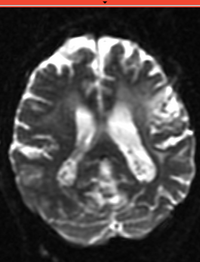

Slicer Registration Library Exampe #3: Diffusion Weighted Image Volume: align with structural reference MRI

This is a typical example of DTI processing. Goal is to align the DTI image with a structural scan that provides accuracte anatomical reference. The DTI contains acquisition-related distortion and insufficient contrast to discern anatomical detail.

• Button red fixed white.jpgreference/fixed : T2w FSE,

• Button green moving white.jpg moving: Baseline image of acquired DTI volume, corresponds to T2w MRI , 0.9375 x 0.9375 x 1.4 mm voxel size, oblique

after orientation

before/after registration, indiv. images in red/cyan, match in gray